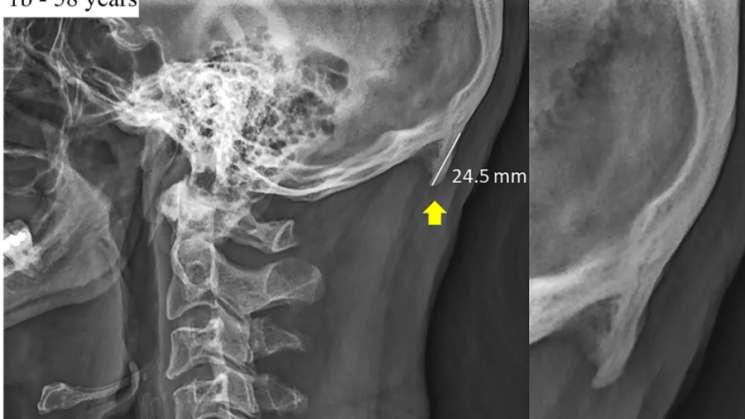

En el primer trabajo, los investigadores analizaron 218 radiografías de personas entre los 18 y 30 años. En el 41% de ellos había crecido un bulto óseo de 10 a 30 milímetros en la parte posterior de su cráneo.

En el estudio de 2018, los investigadores compararon las radiografías de personas jóvenes con otras más adultas y observaron que el crecimiento en la parte posterior del cráneo era más frecuente en los hombres jóvenes que en las personas de mayor edad, siendo incluso, en promedio más grande.